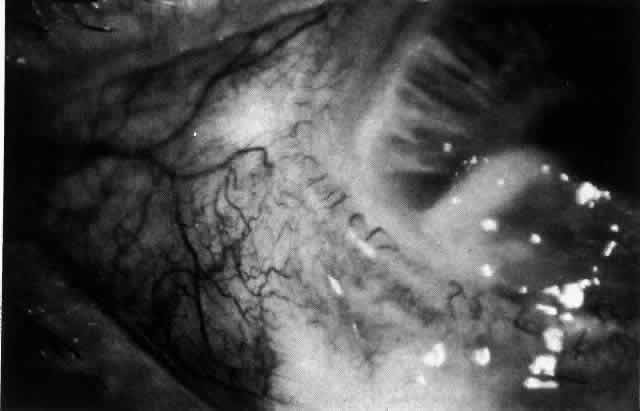

The sclera that is edematous is pushed forward, and the deep episcleral network is more congested than the superficial networks (Figs. 27 and 28). It is usually easy to ascertain by simple observation that the patient has scleritis and not episcleritis. However, it is not as easy to ascertain whether the patient has early necrotizing scleritis. It is in these patients that fluorescein angiography has considerable value, because the first changes are detectable in the ocular vasculature. Prompt and adequate treatment can prevent these changes from becoming irreversible.

Fig. 27. In scleritis, maximum congestion occurs in deep episcleral plexus, which is bowed forward by underlying scleral edema. Episcleral tissue is slightly infiltrated and superficial plexus is slightly congested (see Fig. 14). (Watson PG, Hayreh S, Awdry P: Episcleritis and scleritis. Br J Ophthalmol 52:278–279, 1968)

Fig. 28. Nodular scleritis. Both the anterior conjunctival slit and the deep scleral slit are displaced forward by the scleral edema. There is little separation between these two beams, indicating that all the edema is in the sclera and not in the overlying episclera. (Watson PG, Hayreh S, Awdry P: Episcleritis and scleritis. Br J Ophthalmol 52:278–279, 1968)